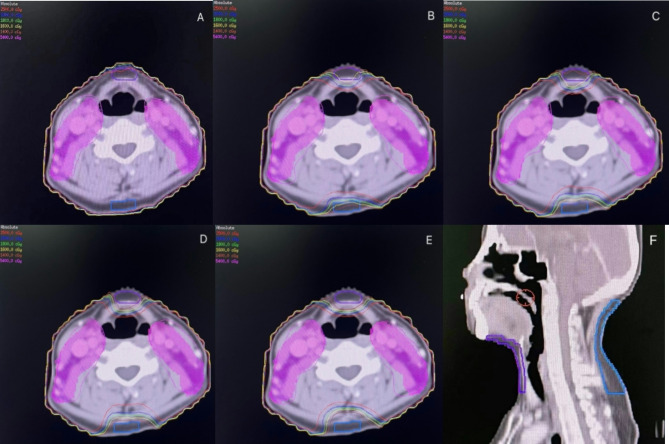

本研究旨在通过在颈部前后区域设置剂量限制环,确定早期鼻咽癌(NPC)接受调强放疗(IMRT)患者减少头颈部淋巴水肿的最佳限制剂量。共纳入15例早期鼻咽癌患者,为每位患者设计5套IMRT方案。方案A为常规方案,不设剂量限制环,方案B-E分别设置梯度为20 Gy、18 Gy、16 Gy、14 Gy的剂量限制环,其余参数与方案A一致。通过随机区组设计数据的方差分析和Bonferroni两两多重比较,评价剂量限制环对靶覆盖率和危及器官剂量的影响,确定最佳剂量限制剂量。之后,对50例早期鼻咽癌患者(25例根据最佳限制剂量有环,25例无环)进行IMRT治疗,以确定头颈部淋巴水肿的发生率是否有差异。最终,16 Gy被确定为达到目标覆盖和保护危险器官平衡的最佳限制剂量阈值。与常规方案相比,设置16 Gy的颈椎前后限剂量环不影响靶剂量覆盖(均P < 0.05),仅轻微影响均匀性指数和增加监测单位(MUs)(均P < 0.05),同时口腔、喉部和甲状腺的剂量明显降低(均P < 0.05)

This study aimed to determine the optimal limiting dose to reduce head and neck lymphedema in patients with early nasopharyngeal carcinoma (NPC) receiving intensity-modulated radiotherapy (IMRT) by setting dose limiting rings at the anterior and posterior regions of the neck. A total of 15 patients with early NPC were included, and 5 sets of IMRT plans were designed for each patient. Plan A was a conventional plan without dose limiting rings, while Plans B-E were set dose limiting rings with gradients of 20 Gy, 18 Gy, 16 Gy, and 14 Gy, respectively, whose remaining parameters were consistent with Plan A. Through Analysis of Variance (ANOVA) for randomized block design data and Bonferroni pairwise multiple comparisons, the impact of dose limiting rings on target coverage and doses to organs at risk was evaluated and the optimal limiting dose was determined. After that, 50 patients with early NPC (25 with rings according to the optimal limiting dose, 25 without rings) were treated with IMRT to determine if there was a difference in the incidence of head and neck lymphedema. Ultimately, 16 Gy was determined as the optimal limiting dose threshold for achieving the balance of target coverage and protection of organs at risk. Compared with the conventional plan, setting cervical anterior and posterior dose limiting rings of 16 Gy did not affect the target dose coverage (all P > 0.05), only slightly affected homogeneity index and increased monitor units (MUs) (both P < 0.05). The doses of the inner ears, mandible, and brainstem were not affected (all P > 0.05), meanwhile, the doses of the oral cavity, larynx, and thyroid were reduced significantly (all P < 0.05). The doses of the parotid glands and spinal cord slightly increased (both P < 0.05), but still within the tolerance range. Clinical cohort verification showed that setting the dose limiting rings of 16 Gy at the anterior and posterior regions of the neck significantly reduced the occurrence of head and neck lymphedema (P < 0.05). Through dosimetric and clinical cohort verification studies, the optimal limiting dose for the cervical anterior and posterior dose limiting rings has been determined, hoping to provide a new design method of IMRT plans to reduce head and neck lymphedema after radiotherapy for early NPC.